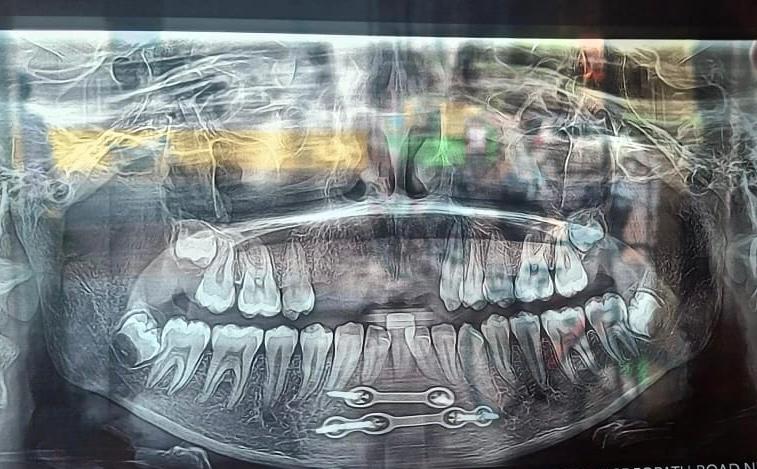

X-rays: Dental X-rays help diagnose issues not visible during a regular examination, such as tooth decay, impacted teeth, and bone loss.